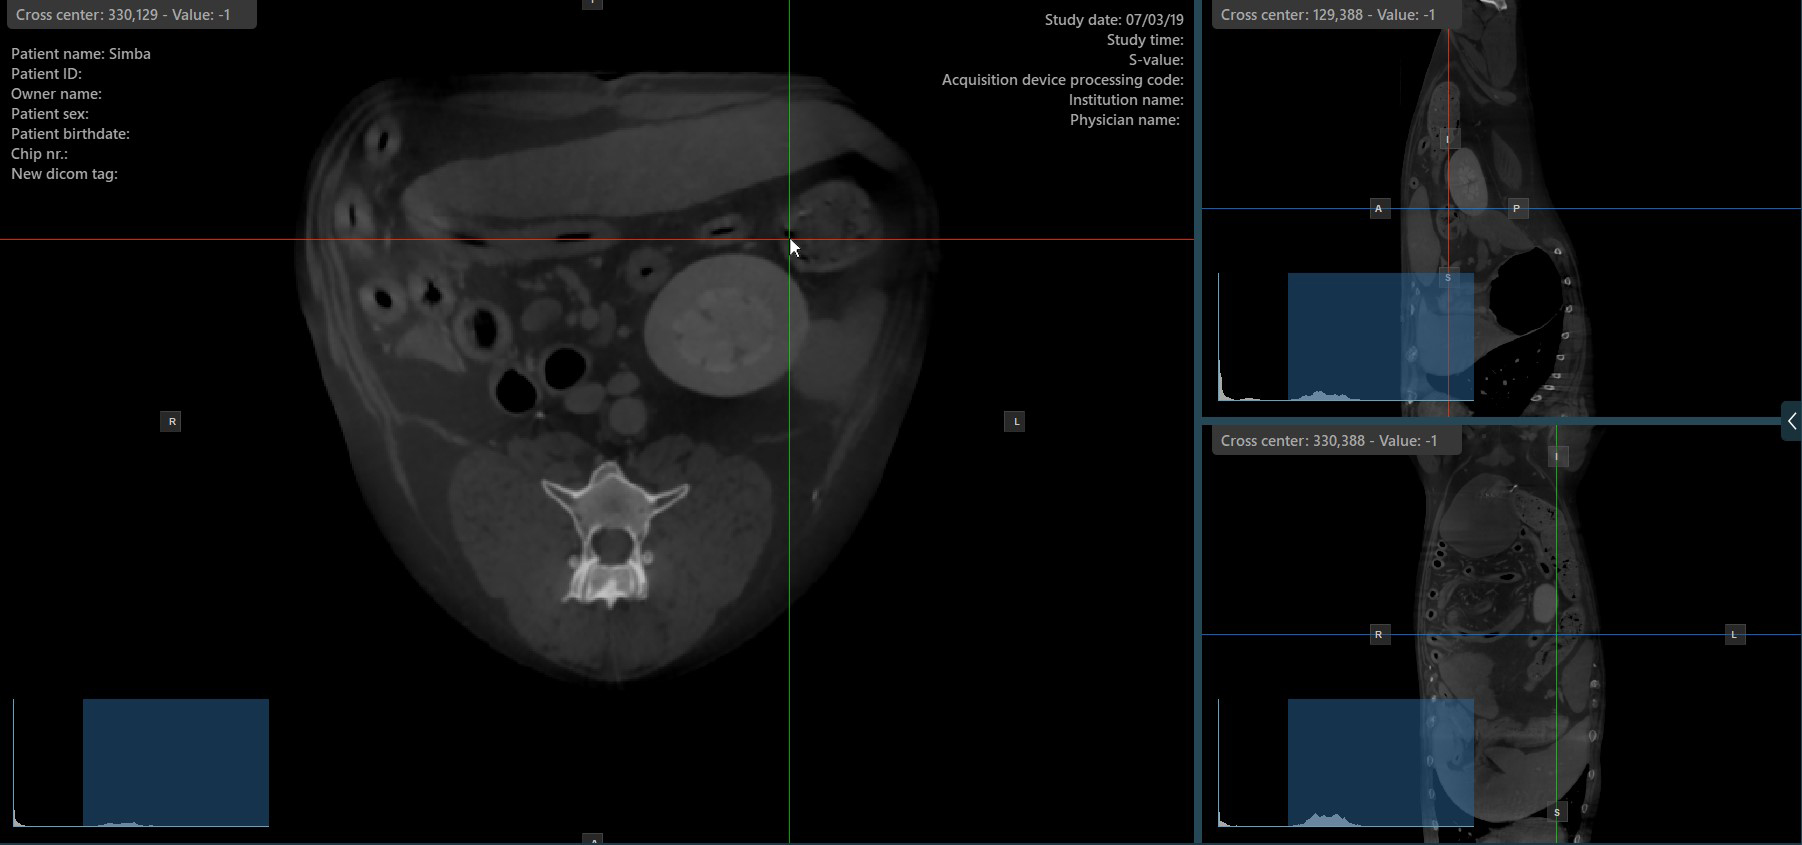

Change Slicers Cross Center Position¶

Altering the position of the cross center of slicers will change the position of the corresponding two image planes. The cross center of the slicers can be selected by using the Select Item (Default) tool, assigned to the right mouse

button by default.

Once selected, drag the cross center of the specific slicers to the desired direction to move its position. The corresponding image planes’ orientation changes accordingly.